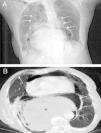

Presentamos el caso de una mujer de 96años con antecedentes de hipertensión arterial y hernia de hiato que consultó por cuadro de dolor epigástrico y vómitos en posos de café de 6h de evolución. En la exploración física se apreciaba distensión abdominal con dolor a la palpación en epigastrio. La radiografía de tórax reveló la presencia de una cámara gástrica distendida en la cavidad torácica y neumomediastino. La TC toracoabdominal (fig. 1) mostró la cámara gástrica distendida a nivel torácico con la unión gastroesofágica y gastroduodenal por encima del hiato esofágico, así como colecciones de aire y líquido a nivel del mediastino y presencia de enfisema subcutáneo. Estos hallazgos eran compatibles con perforación gástrica secundaria a vólvulo en paciente con hernia hiatal gigante. Debido a la avanzada edad de la paciente se descartó la intervención quirúrgica, falleciendo a las pocas horas del ingreso.